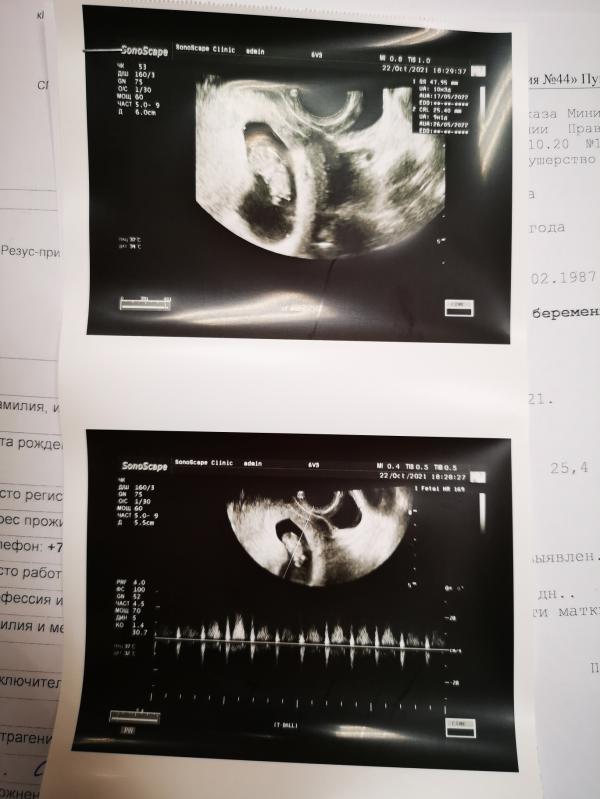

Сходила сегодня на УЗИ, послушала сердечко 😍🥰 Нереальное чувство, когда слышишь первый раз ❤️ Разница со вторым фото 3 недели. Показала нашему папе, улыбнулся, сказал: "Похоже на человека")